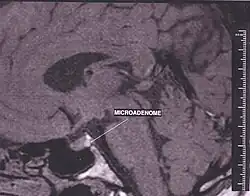

Adenom hypofýzy je benigní (nezhoubný), pomalu rostouci nádor hypofýzy.